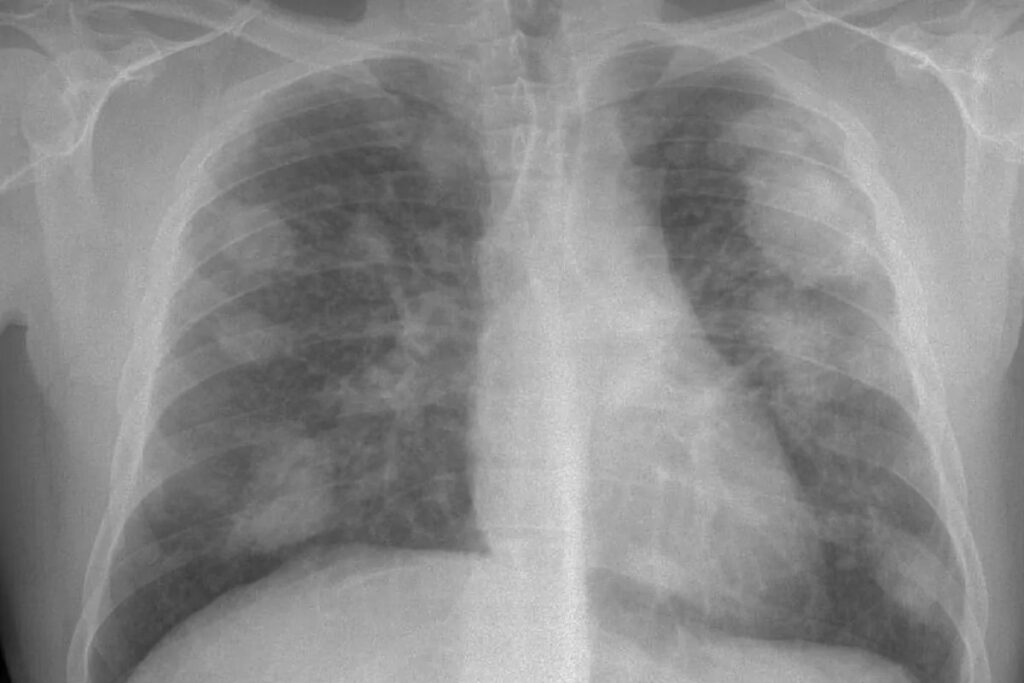

Con el tiempo, esta reacción inflamatoria y fibrótica conduce a la formación de los llamados nódulos silicóticos, pequeñas masas de tejido cicatricial que son el sello distintivo de la enfermedad. A medida que estos nódulos crecen y se fusionan, la capacidad de los pulmones para expandirse y transferir oxígeno a la sangre se ve gravemente comprometida, llevando a una dificultad respiratoria progresiva y, finalmente, a la insuficiencia respiratoria.

- Monitoreo y vigilancia de la salud: Realizar mediciones periódicas de la calidad del aire para asegurar que los niveles de sílice se mantengan por debajo de los límites permitidos y ofrecer programas de vigilancia médica a los trabajadores expuestos, incluyendo radiografías de tórax y pruebas de función pulmonar.